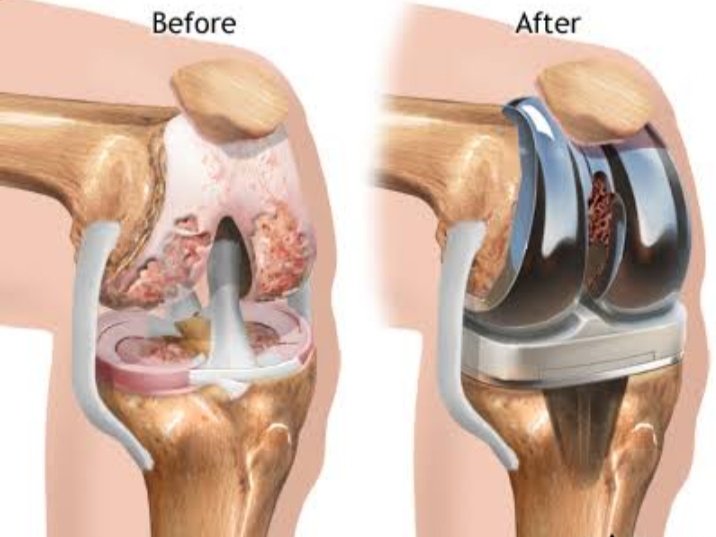

KNEE SURGERY

ACL injuries and Arthroscopic ACL reconstruction with hamstring tendons and Bioabsorable screws, Menisceal injuries and repair, Autologus chondral transplant (OATS), Arthroscopic Synovectomies, Tibial pleatue fractures, Total Knee replacement (TKR)